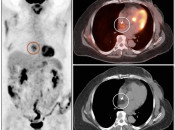

LHIAS is focal fatty infiltration of the inter-atrial septum of the heart.  It behaves as hypermetabolic brown fat, and is often intensely FDG-avid, appearing mass-like on the PET images.

Diagnosis of this hypermetabolic PET finding is confirmed by the presence of only fat on the co-registered CT images.

Misdiagnosis of this “Aunt Minnie” is unacceptable (as in the terrified patient referred to us from Europe, who flew in with his images to further evaluate his “heart cancer”).

Although benign, we recommend mentioning this finding in the body of the report, as it often looks impressive on the PET images and can prompt a call from a clinician concerned that you “missed” a mass.